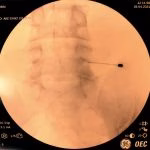

- Rizotomia percutânea lombar

- Implante de neuroestimulador medular

- Bloqueios anestésicos